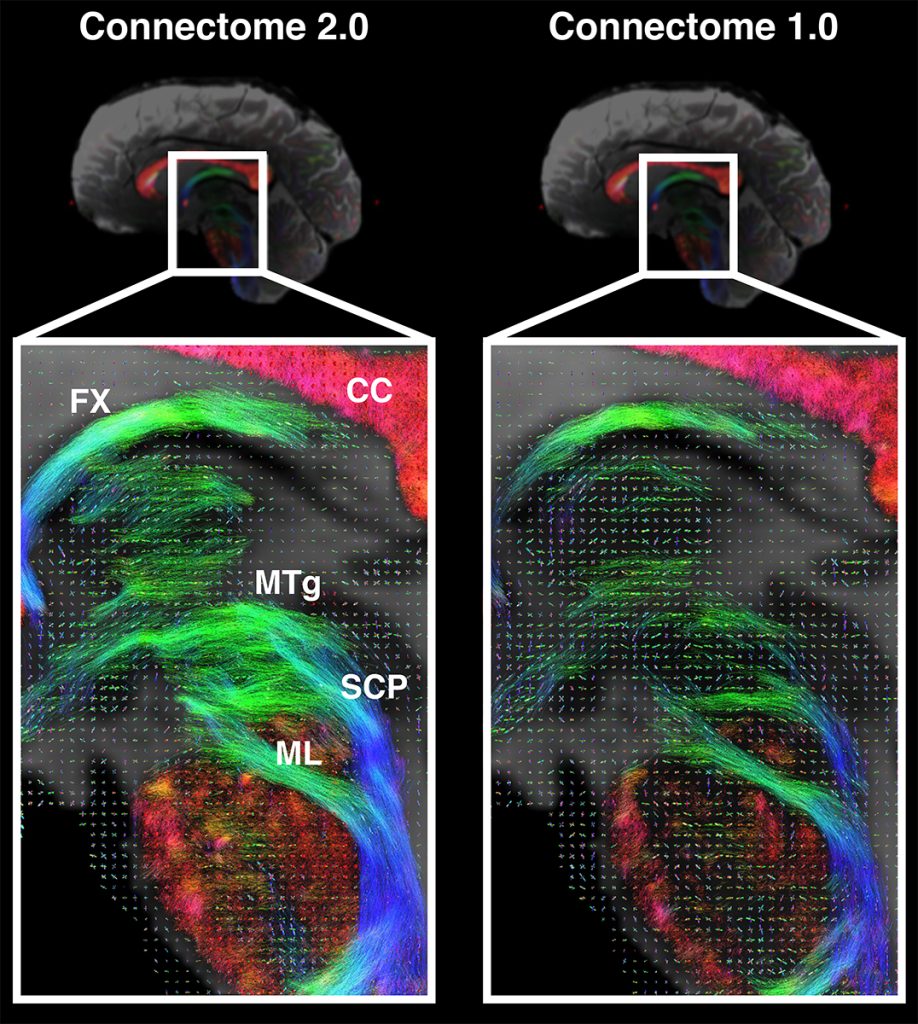

Researchers Create Advanced MRI Scanner to Identify Tiny Brain Structures

Next-Generation Imaging for Brain Disorders A research team, partly funded by the National Institutes of Health (NIH), has introduced a groundbreaking brain imaging system. This ultra-high-resolution technology aims to reconstruct minute brain structures that are often compromised in various neurological and mental health conditions. Compared to traditional magnetic resonance imaging (MRI), this new system offers […]